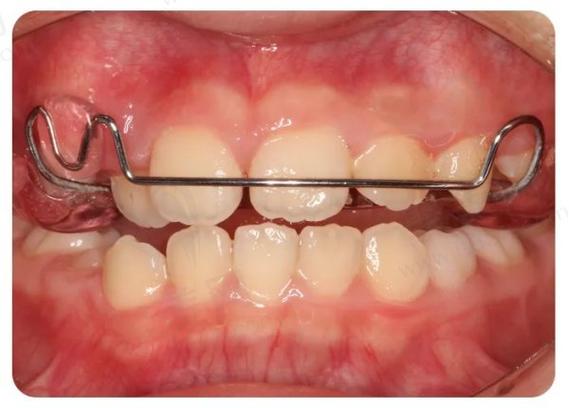

(图片来源网络,侵删)- 骨开裂或骨皮质穿孔: 尤其是在上颌骨,扩弓器施加的力量过大或时间过长,可能导致牙槽骨的骨皮质(骨表面坚硬层)开裂甚至穿孔,这会破坏骨组织的完整性,影响牙齿的长期稳定性。

(图片来源网络,侵删)- 颊部软组织张力过大: 牙弓过度扩大可能使颊部肌肉和软组织被过度拉伸,导致患者感觉脸颊“鼓胀”、“不自然”,甚至影响发音和进食。

牙齿过度颊倾、牙龈退缩、牙根暴露、颊部鼓胀等都会显著影响面部美观。